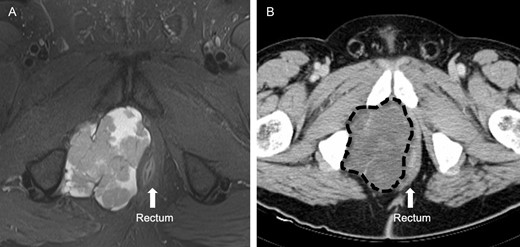

A 51-year-old Caucasian male with 20-year history of UC presents with decreased stool caliber, inability to empty completely, as well as bloody stools. His UC was well controlled until the previous year, at which point he required the addition of oral mesalamine and hydrocortisone suppositories. Recent colonoscopy visualized left-sided disease, and biopsies did not reveal any dysplasia. Magnetic resonance imaging (MRI) and computed tomography (CT) showed a large soft tissue mass in the right ischiorectal fossa with mass effect on the pelvic diaphragm muscles, prostate and rectum (Fig. 1). It had the appearance of a soft tissue sarcoma. However, CT-guided percutaneous biopsy of the mass revealed a cylindroma-like basaloid carcinoma of the anal region. It was at Stage II, T3N0M0, according to American Joint Committee on Cancer guidelines. He received 5 weeks of radiation (54 Gy), plus chemotherapy with 5-fluorouracil (5FU) and mitomycin C during Weeks 1 and 5 of radiation with only a modest response (20%). Extirpation was planned. Given his history of UC, we performed total colectomy and end ileostomy in conjunction with wide abdominoperineal resection of the tumor. Genitourinary structures and the bony pelvis were spared. We reconstructed his perineum with a rectus abdominis myocutaneous flap from the left abdomen, and the omentum was used to obliterate pelvic space. The ileostomy was placed on the right abdomen (Fig. 2).

(A) This is a MRI T2-weighted image before neoadjuvant therapy. The light area clearly delineates the large heterogeneous mass in the right ischiorectal fossa. The rectum is displaced to the left. (B) This is a CT image of the same mass after neoadjuvant therapy, marked by dashed line.